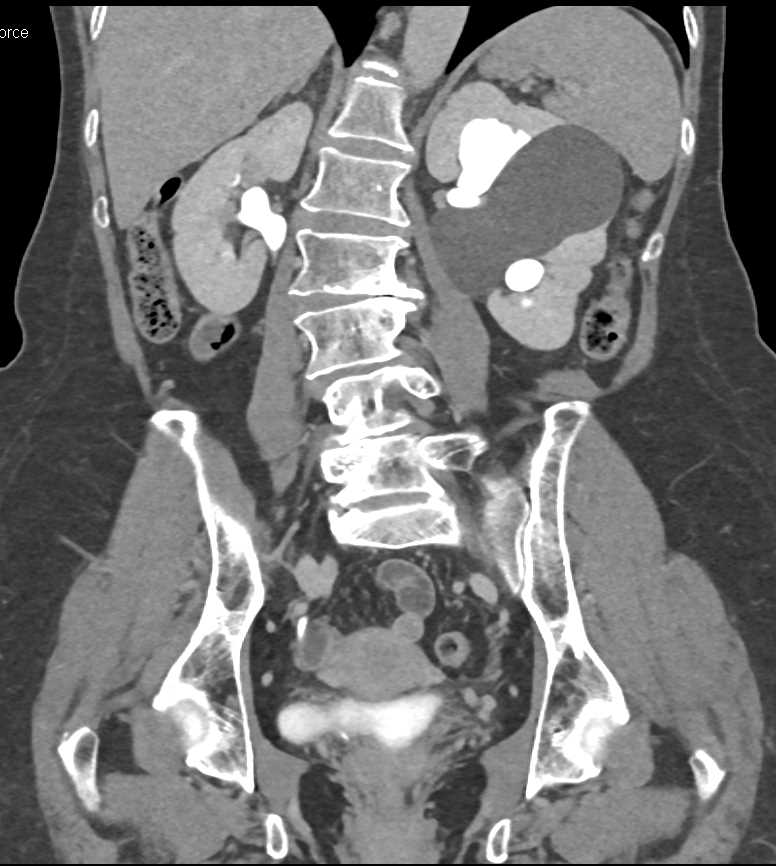

Parapelvic Cysts Left Kidney